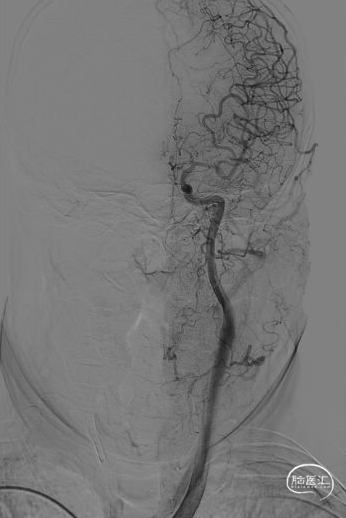

弓造影:主动脉弓II型。

左椎造影:左侧椎动脉全程走形严重迂曲,基底动脉纤细。

左椎造影:左侧颈内动脉走形尚可,C4-C7段管壁欠光滑,C4段管腔轻度狭窄,约25%;C6段管腔轻度狭窄,约45%;左侧大脑前动脉走形尚可,A1-A2段管壁欠光滑;左侧大脑中动脉走形尚可,管壁欠光滑,M1段管腔重度狭窄,约90%,长约10mm,不除外夹层可能;左侧大脑前动脉通过软脑膜向右侧大脑中动脉供血区代偿供血,代偿分级2级。

左颈造影:左侧颈内动脉走形尚可,C4-C7段管壁欠光滑,C4段管腔轻度狭窄,约25%;C6段管腔轻度狭窄,约45%;左侧大脑前动脉走形尚可,A1-A2段管壁欠光滑;左侧大脑中动脉走形尚可,管壁欠光滑,M1段管腔重度狭窄,约90%,长约10mm,不除外夹层可能;左侧大脑前动脉通过软脑膜向右侧大脑中动脉供血区代偿供血,代偿分级2级。

右颈造影:右侧颈内动脉C1、C6-C7段走形迂曲,C4-C7段管腔欠光滑,C4后膝部可见一宽颈瘤样突起(颈7.55mm,长3.32mm),C4段前膝、C7段轻度狭窄,约10%;右侧大脑中动脉M1段走形迂曲,管壁欠光滑,M1远端中度狭窄,约50%,M1近端可见一宽颈瘤样突起(颈5.17mm,长1.35mm);右侧大脑前动脉A1-A2段走形迂曲,前交通开放,向右侧大脑前动脉供血。

右椎造影:右侧椎动脉全程走形迂曲,管腔光滑,管腔未见明显狭窄及斑块。

2、DSA:左侧大脑中动脉M1段管腔重度狭窄,约90%,长约10mm,不除外夹层可能。